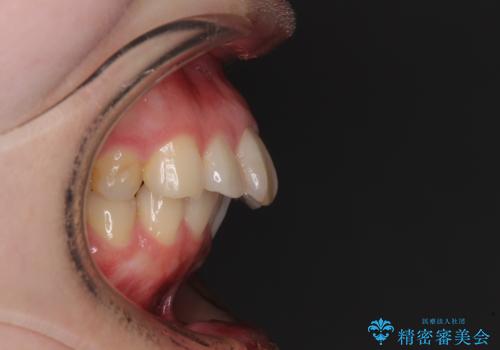

奥歯の咬み合わせを見ると、上顎が下顎に対して相対的に前方にありました。

口元の閉じにくさを改善するためには、上顎臼歯を後方に移動させた咬み合わせにする必要があります。